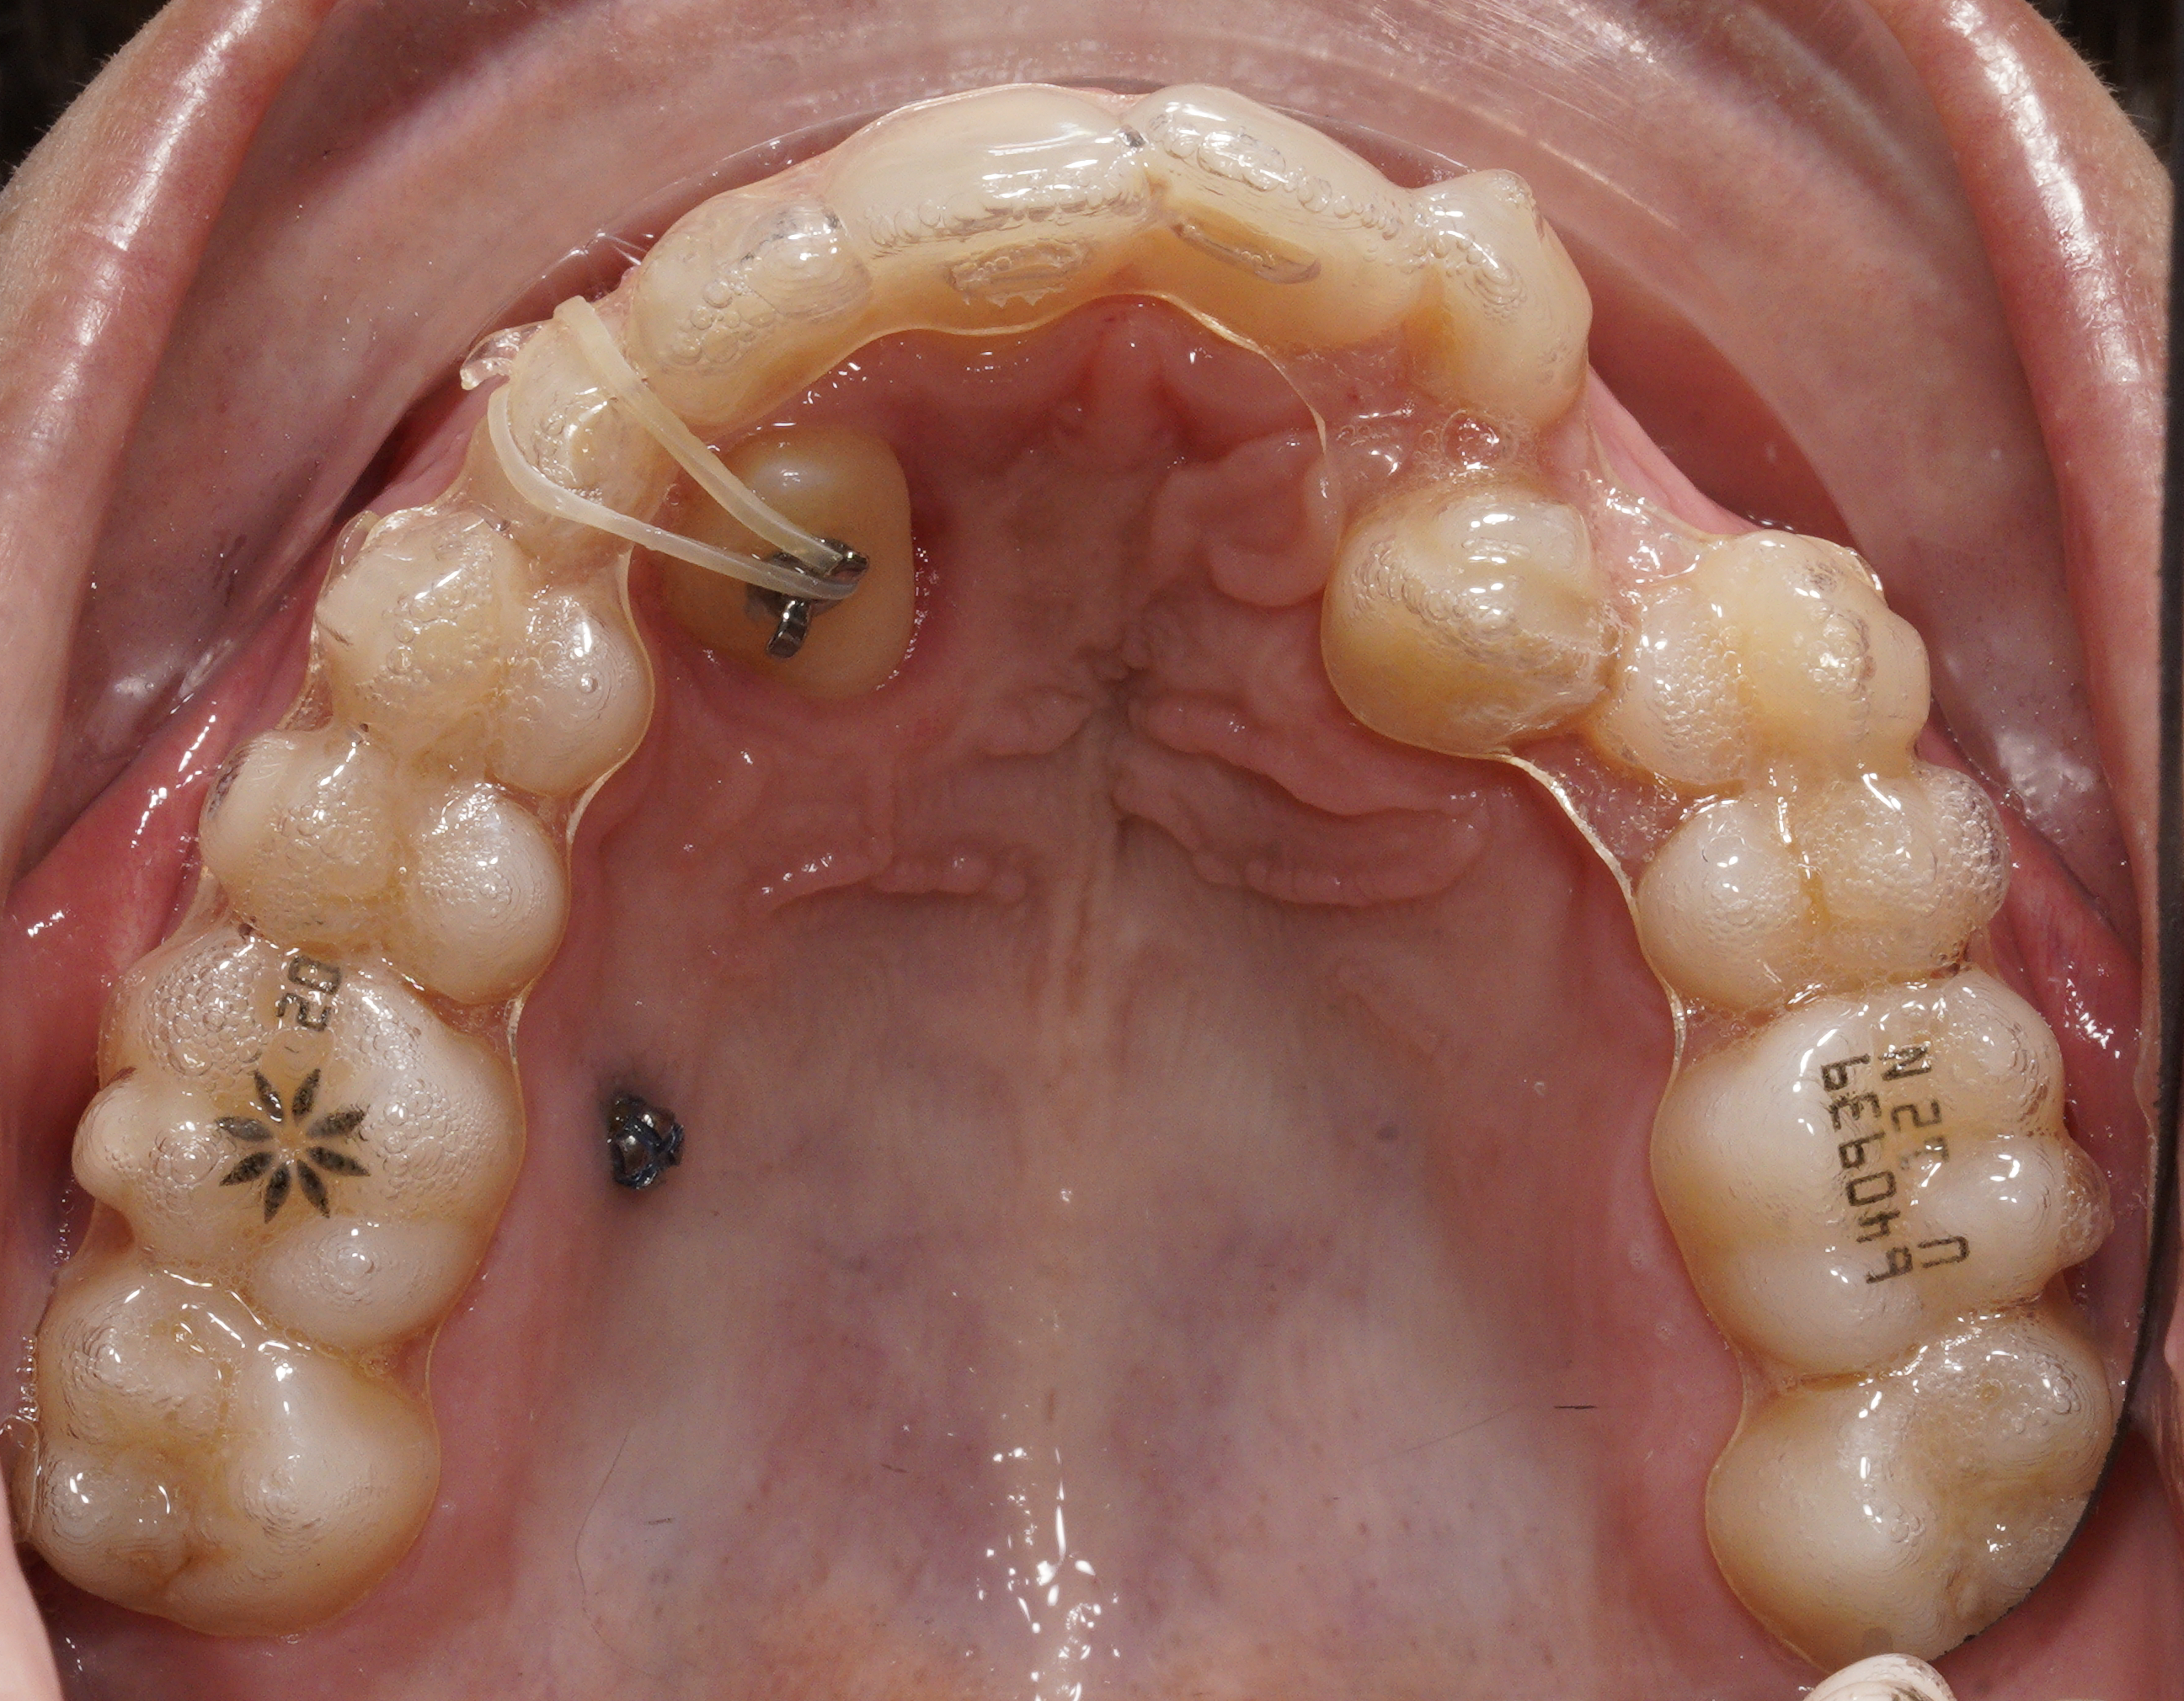

Integrazione digitale e allineatori

Dopo il recupero palatale, è iniziata la fase con allineatori trasparenti, sfruttando il software ClinCheck® Pro e l'integrazione dei dati della CBCT.

- Gestione del 13: data la posizione estremamente palatale, inizialmente non è stato incluso nell'allineatore. È stato avvicinato alla corretta posizione vestibolare mediante un elastico a cavaliere.

Evoluzione del trattamento e refinement

Il percorso terapeutico ha richiesto un monitoraggio costante:

- Fase 23: una nuova scansione ha permesso di includere il 13 negli allineatori. A causa dell'esiguità di spazio, non è stato possibile applicare un attachment rettangolare su questo elemento.

- Fase 40: si è verificato un misfit proprio sul 13. È stato quindi eseguito un terzo set di 32 allineatori per rifinire la posizione e consolidare il risultato.